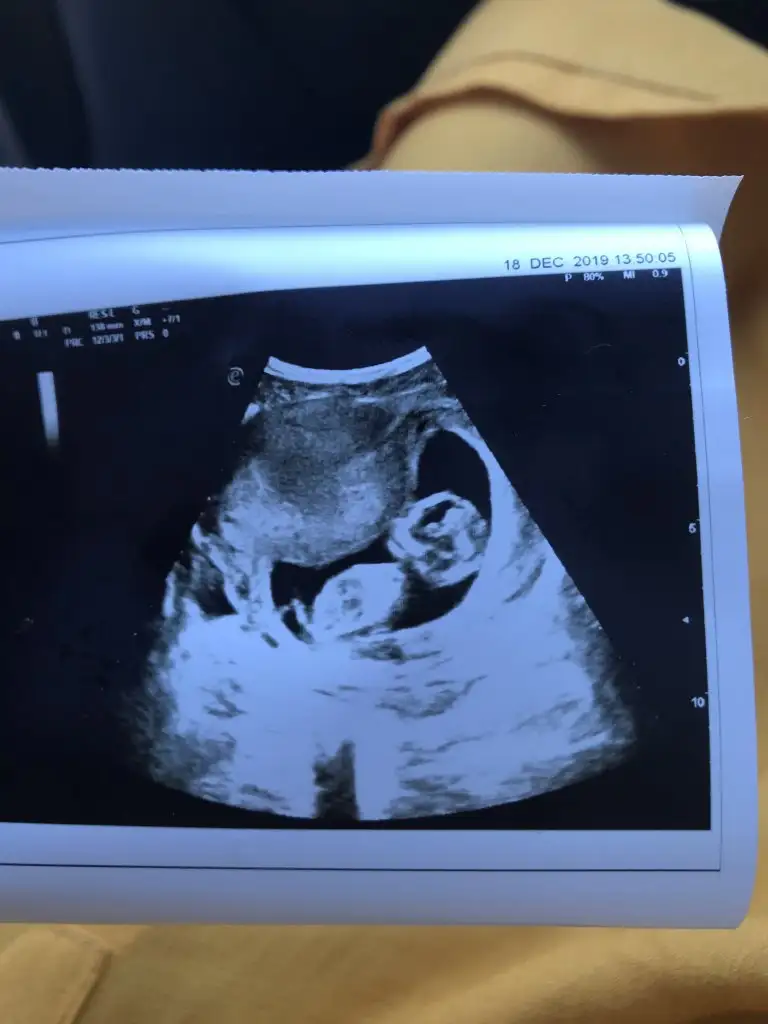

Ikra meyra Ikra meyra canım burda 12+2 ultrasona göre. Tekrar gönder demiştin var mı acaba bi şansım bu sefer 😂

Eklentiler

• IMG-20191218-WA0017.webp

IMG-20191218-WA0017.webp

14,8 KB · Görüntüleme: 89

• IMG-20191218-WA0018.webp

IMG-20191218-WA0018.webp

15,9 KB · Görüntüleme: 100